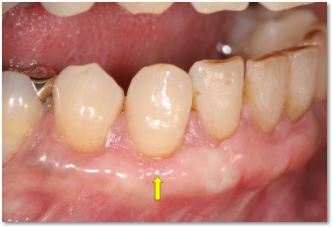

治療例1:結合組織移植による根面被覆の症例

歯ぐきが下がってしまっています。(

↑

)

見た目にも問題があります。